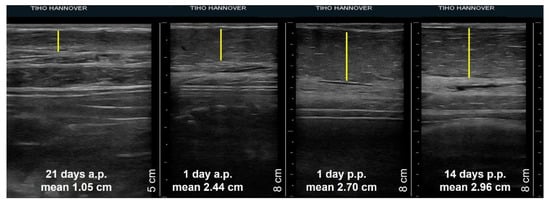

Comparing the thickness of different tissues of the mammary glands on single examination days, there were no differences due to their position or between the glands of sows of different parity. Therefore, the mean values of the width of glands tissues of sows on specific days of pregnancy and lactation were calculated and compared. Figure 4 shows an example of the increase in thickness of the mammary parenchyma measured from ultrasonographic images in the period from day 21 a.p. and day 14 p.p.

Figure 4.

Four sonograms of a sow´s third mammary gland showing the thickness of the parenchyma (yellow line) at day 21 a.p., day 1 a.p., day 1 p.p., day 14 p.p. Mean values represent the mean thickness of the gland parenchyma of all sows during the specific day of pregnancy or lactation.

The thickness of the udder skin increased from 0.18 cm ± 0.04 cm on day 21 a.p. to 0.27 cm ± 0.08 cm on day 1 a.p. (Figure 5a). Subsequently, the layer thickness decreased to 0.24 cm ± 0.05 cm up to day 14 p.p. The width of the muscle layer continuously increased on average by 0.7 cm from 1.37 cm ± 0.39 cm to 2.07 cm ± 0.63 cm at day 14 p.p. over the whole observation period (Figure 5b). The increase in thickness of both tissue layers was not statistically significant. In contrast, the parenchyma increased significantly during ante partum from 1.05 cm ± 0.24 cm on day 21 a.p. to 2.44 cm ± 0.57 cm on day 1 a.p., followed by a lower growth to 2.96 cm ± 0.89 cm by day 14 p.p. (Figure 5c).